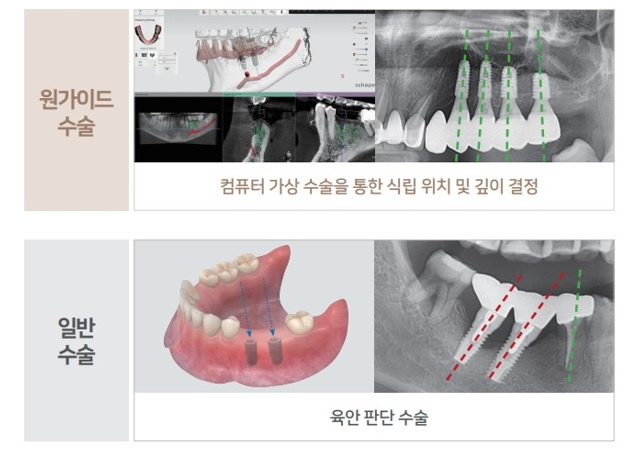

일반 임플란트 수술과의 차이점은?!

컴퓨터 가상 수술을 통해 최적의 임플란트 식립 위치 및 깊이를 미리 결정하고

가이드를 제작, 구강에 장착하여 수술하기 때문에 육안으로 판단하는 일반 수술 대비

정확도가 매우 높고 안전하며 빠른회복이 가능합니다